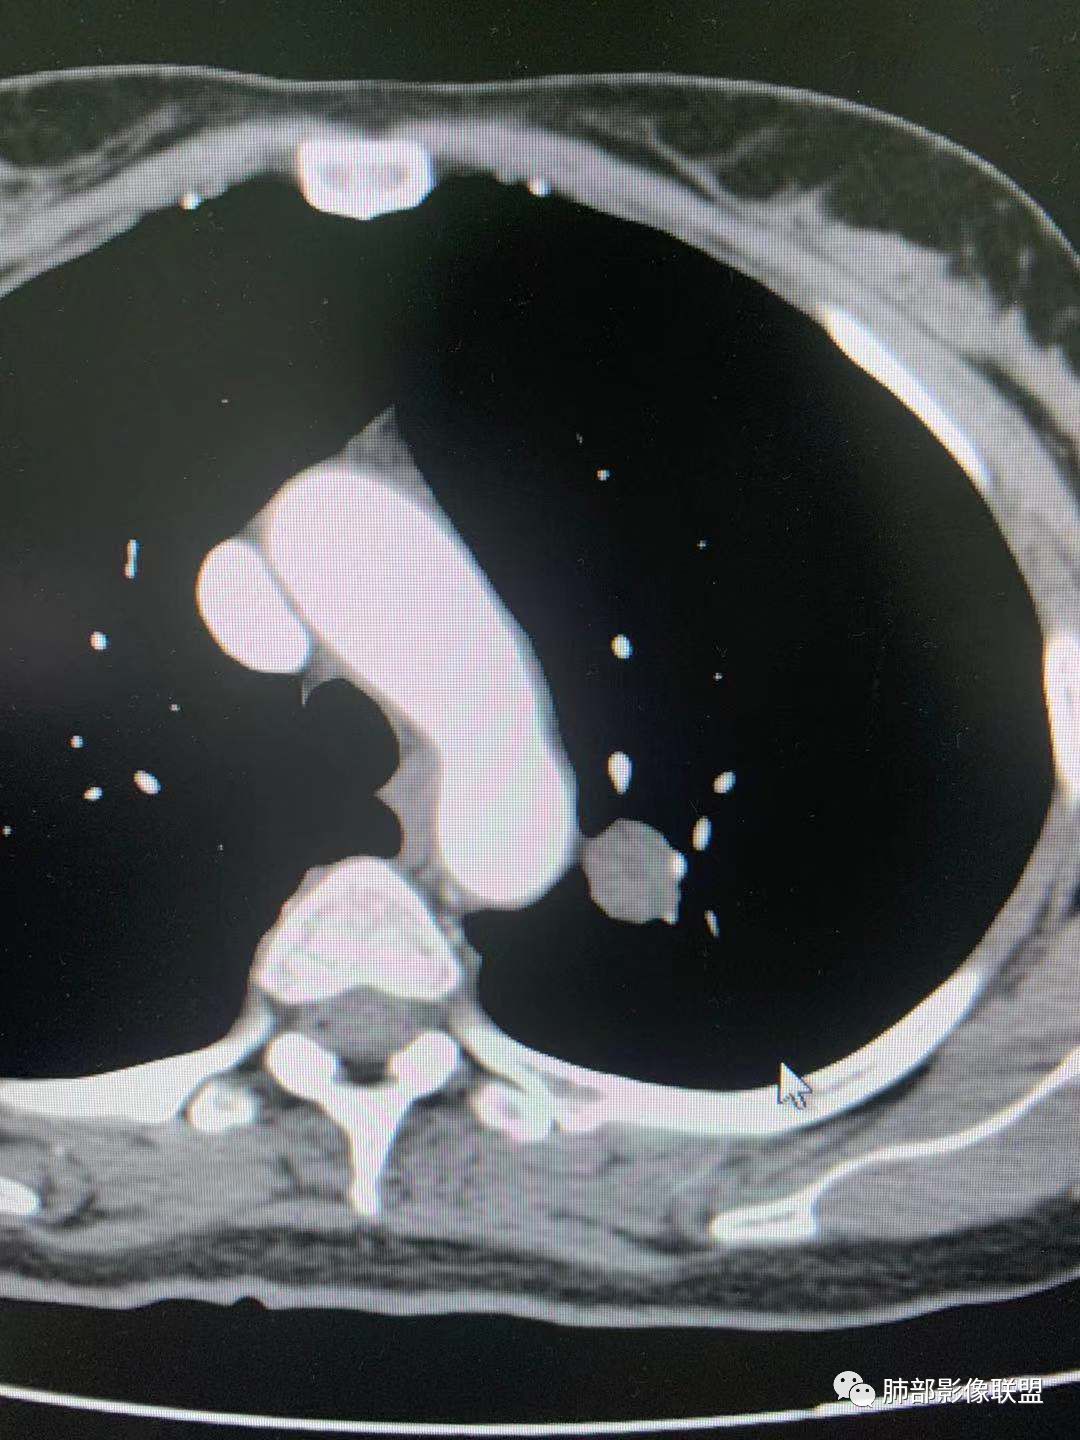

CT值30HU;增强后:41/76HU

强化幅度:46HU

边缘平直,延迟强化,血管贴边,支气管推移,毛刺较软,收缩力较弱。

蓝天白云

血管贴边